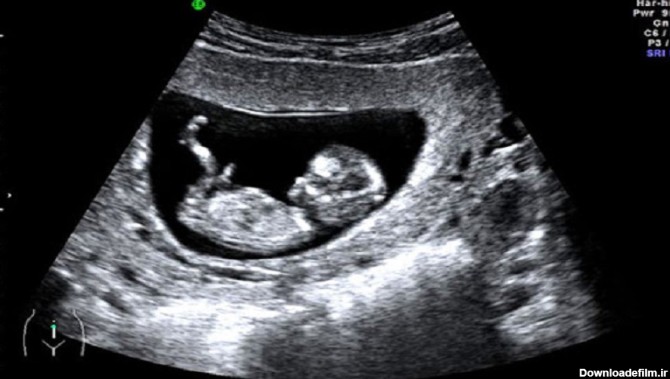

عکس غربالگری اول جنین دختر

عکس جنین دختر و پسر در سونوگرافی از نظر نوع و شکل آلت تناسلی با یکدیگر اختلاف دارد. در پسرها شامل بیبضه و در دختر ها شامل لبیا است.

تعیین جنسیت جنین با سونوگرافی در هفته 12 بارداری در این مرکز با ضریب اطمینان 99% قابل انجام است که در این سن ، دقیقترین در ایران میباشد.